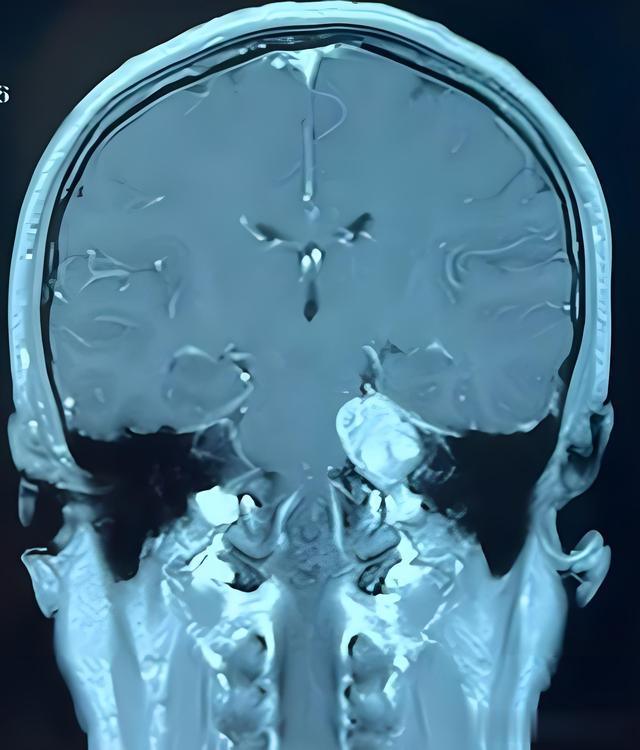

听神经瘤,又称前庭神经鞘瘤,起源于听神经鞘膜,是桥小脑角区最为常见的肿瘤,约占颅内肿瘤的 8%-10% 。其年发病率约为 1-2/10 万 ,且随着磁共振成像(MRI)技术的广泛应用,微小听神经瘤的检出率已提升至 65% 。手术切除目前仍是治疗听神经瘤的主要手段,其核心目标在于实现较高的肿瘤全切除率、良好的面神经解剖保留率以及一定比例的听力保留率。有研究表明,理想的手术效果应达到肿瘤全切除率>95% ,面神经解剖保留率>90% ,听力保留率达 30%-50% 。然而,由于听神经瘤所处位置毗邻众多重要的神经和血管结构,手术操作极具挑战性,因此不断探索和改进手术方法与技术具有至关重要的意义。本文将全面梳理听神经瘤手术方法的演变历程以及技术创新点。

乳突切除:在进行乳突切除时,需精心操作以保留外耳道后壁的完整性。这不仅有助于维持耳部的正常解剖结构,减少术后耳部并发症的发生,还能为后续的手术操作提供稳定的支撑。例如,在一项回顾性研究中,对采用经迷路入路手术的患者进行分析,发现保留外耳道后壁完整性的患者,术后耳部感染等并发症的发生率明显低于未保留者。解剖标志识别:准确识别后半规管作为关键的解剖标志至关重要。后半规管的位置相对固定,通过确定其位置,可以为后续对内听道及肿瘤的定位提供重要参考。在实际手术操作中,利用高分辨率的显微镜和精细的器械,能够清晰地分辨后半规管的形态和位置,从而确保手术的准确性。内听道后壁磨除:内听道后壁的磨除范围必须达到肿瘤基底,以充分暴露肿瘤,便于完整切除。但在磨除过程中,需严格控制磨除的深度和范围,避免损伤周围重要的神经和血管结构。有研究报道,通过精确控制内听道后壁磨除范围,肿瘤全切除率得到了显著提高,同时减少了手术相关并发症的发生。

骨窗位置优化:优化骨窗位置是提高手术效果的重要环节。骨窗上界应达到横窦,下界与乙状窦沟平齐。这样的骨窗位置能够提供足够的手术操作空间,同时减少对周围重要结构的不必要暴露。例如,通过对不同骨窗位置的手术效果进行对比研究发现,采用优化后的骨窗位置,手术视野更加清晰,肿瘤切除更加彻底,且对周围神经和血管的损伤风险降低。岩静脉处理:在切开蛛网膜时,要谨慎操作以保留岩静脉的完整性。岩静脉在桥小脑角区的静脉回流中起着重要作用,损伤岩静脉可能导致局部静脉回流障碍,引发脑水肿等并发症。在实际手术中,借助神经电生理监测技术,能够准确判断岩静脉的位置和功能状态,从而避免在手术操作中对其造成损伤。面神经监测:面神经监测是保障面神经功能的关键措施。采用 1-2mA 的刺激强度进行面神经监测,能够及时发现面神经的功能变化,指导手术操作。研究表明,通过精确的面神经监测,面神经解剖保留率得到了显著提高,患者术后面瘫等并发症的发生率明显降低。

大型肿瘤切除效果提升:对于大型肿瘤(>3cm),神经内镜辅助显微手术的切除率可提升至 98% 。神经内镜能够提供更广阔的视野,帮助术者观察到肿瘤与周围组织的复杂解剖关系,从而更彻底地切除肿瘤。例如,在对一组大型听神经瘤患者的手术治疗中,采用神经内镜辅助显微手术,肿瘤全切除率明显高于传统手术方式。减少术野死角:该技术能够有效减少术野死角,使手术视野更加清晰。研究表明,神经内镜辅助显微手术可使术野死角减少 67% ,有助于提高手术的精准性和安全性。在手术过程中,通过内镜的多角度观察,能够发现并处理传统显微镜下难以观察到的肿瘤残留组织和潜在的出血点。3.2.2 设备要求